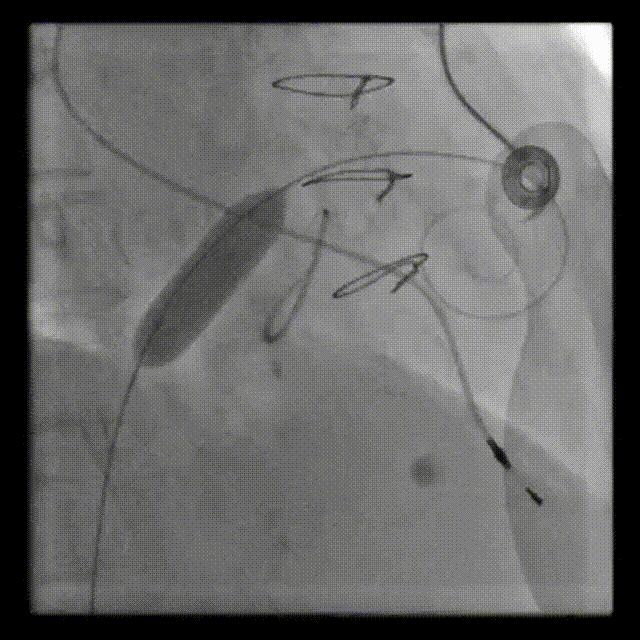

RAO:23° CRA:25°

Positioning heigh: 90/10 preferred